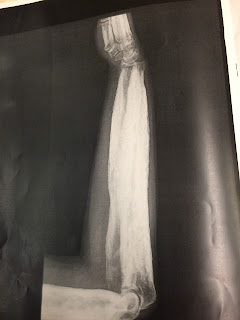

Radiología: se caracteriza por un engrosamiento cortical de la diáfisis de aspecto fusiforme, que puede extenderse y afectar a las metáfisis pero nunca se afectan las epífisis. El canal medular se muestra estrecho

Radiografía anteroposterior del húmero derecho en la que apreciamos una hiperostosis en la diáfisis y metáfisis de este, respetando las epífisis. También podemos observar una disminución del canal medular de dicho hueso.